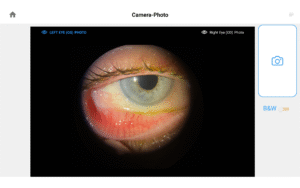

Pushing ahead, our imaging system includes our new, patent-pending Halo background light. Working with native slit lamp illumination, Halo delivers unparalleled clarity of the ocular adnexa. You’ll uncover details of the meibomian glands, acinar spaces, conjunctiva, lid margins, and lashes like never before.